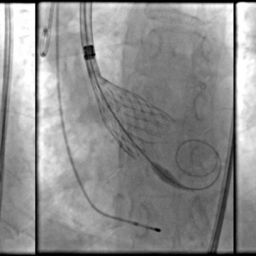

As cirurgias cardiovasculares eletivas estão associadas a pacientes de alto risco cardiovascular e que, na maioria das vezes, precisam ser submetidos a cirurgias não cardíacas. Outra diretriz que recentemente trouxe atualizações sobre esse tema foi a diretriz AHA/ACC de 2024, detalhando alguns critérios a serem avaliados para a indicação de cirurgia de revascularização em paciente de alto risco:

- Paciente com doença arterial coronariana (DAC) instável – com escore GRACE (que avalia risco de morte ou infarto agudo do miocárdio em pacientes com síndrome coronariana aguda) > 140; angina refratária e instabilidade hemodinâmica.

- Tronco esquerdo com estenose acima de 50%, mesmo sem sintomas graves.

- DAC multiarterial com oclusão maior que 70% e disfunção de ventrículo esquerdo.

Com relação a cirurgias valvares, a diretriz recomenda que estenose aórtica grave sintomática, estenose mitral severa com sobrecarga de pressão pulmonar (pressão sistólica da artéria pulmonar > 50 mmHg) ou regurgitações valvares severas com disfunção ventricular sejam tratadas antes de cirurgias não cardíacas de alto risco[4].